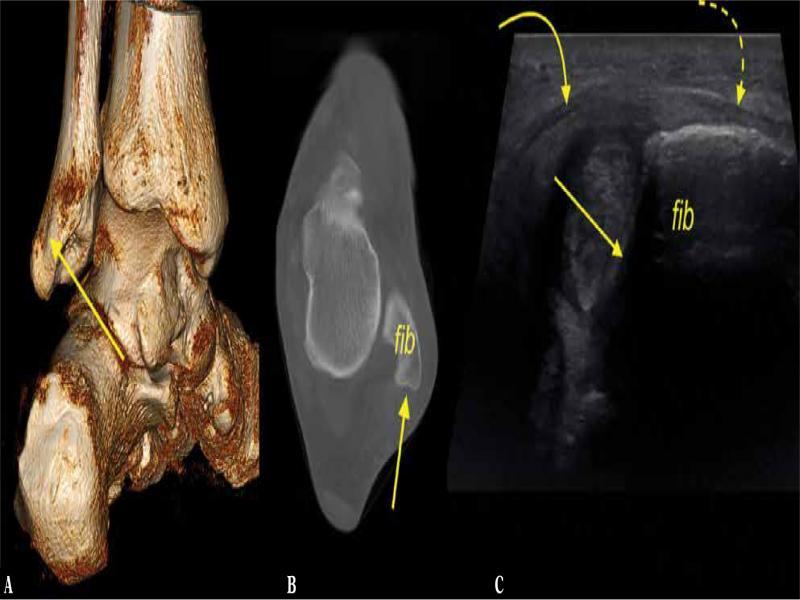

Fig. 7.

Anatomical variations of the peroneal tubercle, three different patients. A, B, C. coronal sections, ultrasound, A. no explicit peroneal tubercle was noted (X), B, C. the peroneal tubercle (t) was present. The peroneus brevis (curved arrow) and the peroneus longus (dashes curved arrow)

In most cases, the peroneal tubercle was found both on US and CT (65.1% and 63.5%, respectively) (Tab. 2, Fig. 8); however, no hypertrophy of the peroneal tubercle was observed. US showed the peroneal tubercle presence in 1.6% cases more compared to CT (p <0.05). We identified 6 cases (9.5%) with os peroneum present on CT while only 3 (4.8%) of them were detected on US (p >0.05). Low-lying peroneus brevis muscle belly was identified in 7 cases (11.1%) on US and in 5 cases on CT (7.9%), p <0.05. No case of peroneus quartus or tertius muscle was found.

Fig. 8.

The most common variant of the retromalleolar fibular groove, convex (straight arrow). A 39-year-old patient with a suspicion of rheumatoid arthritis. A, B. cone-beam computed tomography ( A. 3D posterior medial view, B. transverse section), C. transverse ultrasound section. SPR (curved arrow) was connected (dashed curved arrow) to IER (not shown). Fib – the lateral malleolus